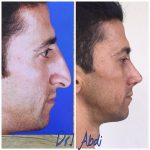

دکتر عیسی عبدی در رشت

دکتر عیسی عبدی در رشت

– متخصص جراحی فک , پلاستیک صورت و بینی

جراحی فک , پلاستیک , صورت وبینی

جراحی ترمیمی و زیبایی فک و صورت و جمجمه و گردن